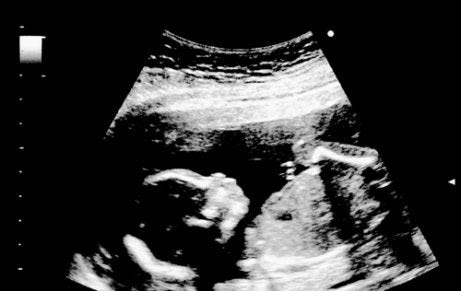

Under ett ultraljud kan du få se barnet röra sig. Han eller hon sträcker på sig och drar in sina armar och ben. Du kan också se fostret öppna och stänga munnen när han eller hon lär sig att svälja.

Under ett ultraljud kan föräldrarna få chansen att se sitt barn suga på sina fingrar.